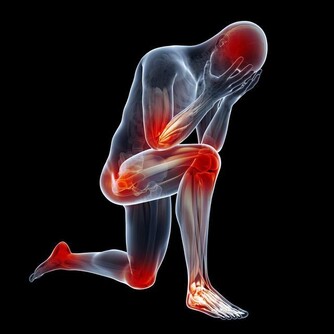

2. 你會出現肌肉痙攣

鉀對肌肉的有效運作至關重要,所以當鉀水平低時,你可能會覺得疼痛,甚至痙攣痛。

1. 你的肌肉感覺無力

鉀對於血糖轉化為糖原(一種儲存在肌肉和肝臟中的燃料)是必不可少的,因此當血糖水平低時,你可能會一整天在學習或工作時感受肌肉無力。另外,鉀水平較低也可能導致尿液中排泄過多的鈣,這也會影響你的骨骼健康。